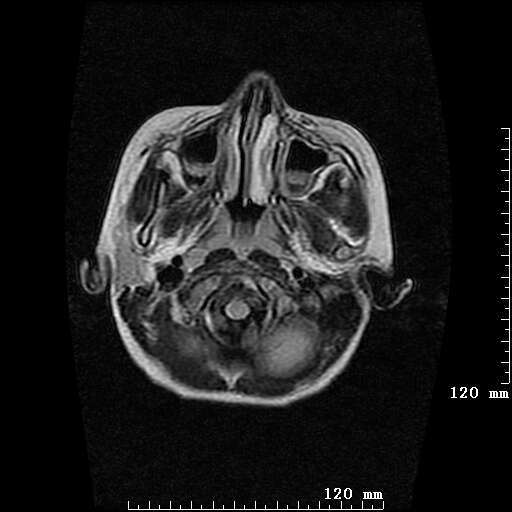

女,7岁,三岁才说话、走路。现智力尚可,走路不稳。临床怀疑大脑发育不全。

考虑 脑白质发育不良

脑折质变薄,双侧侧脑室稍扩张,支持考虑脑折质发育不良

侧脑室周围白质软化症。

考虑胼胝体发育不全,髓鞘形成不良。

支持考虑胼胝体发育不全,髓鞘形成不良。

脑裂畸形伴灰质异位

侧脑室周围白质数量减少,侧脑室不对称性扩大,左侧侧脑室后角呈方形改变,脑沟加深,结合临床考虑脑室周围白质软化症(pvl)。期待结果!

只看出灰质异位

支持脑白质发育不良。